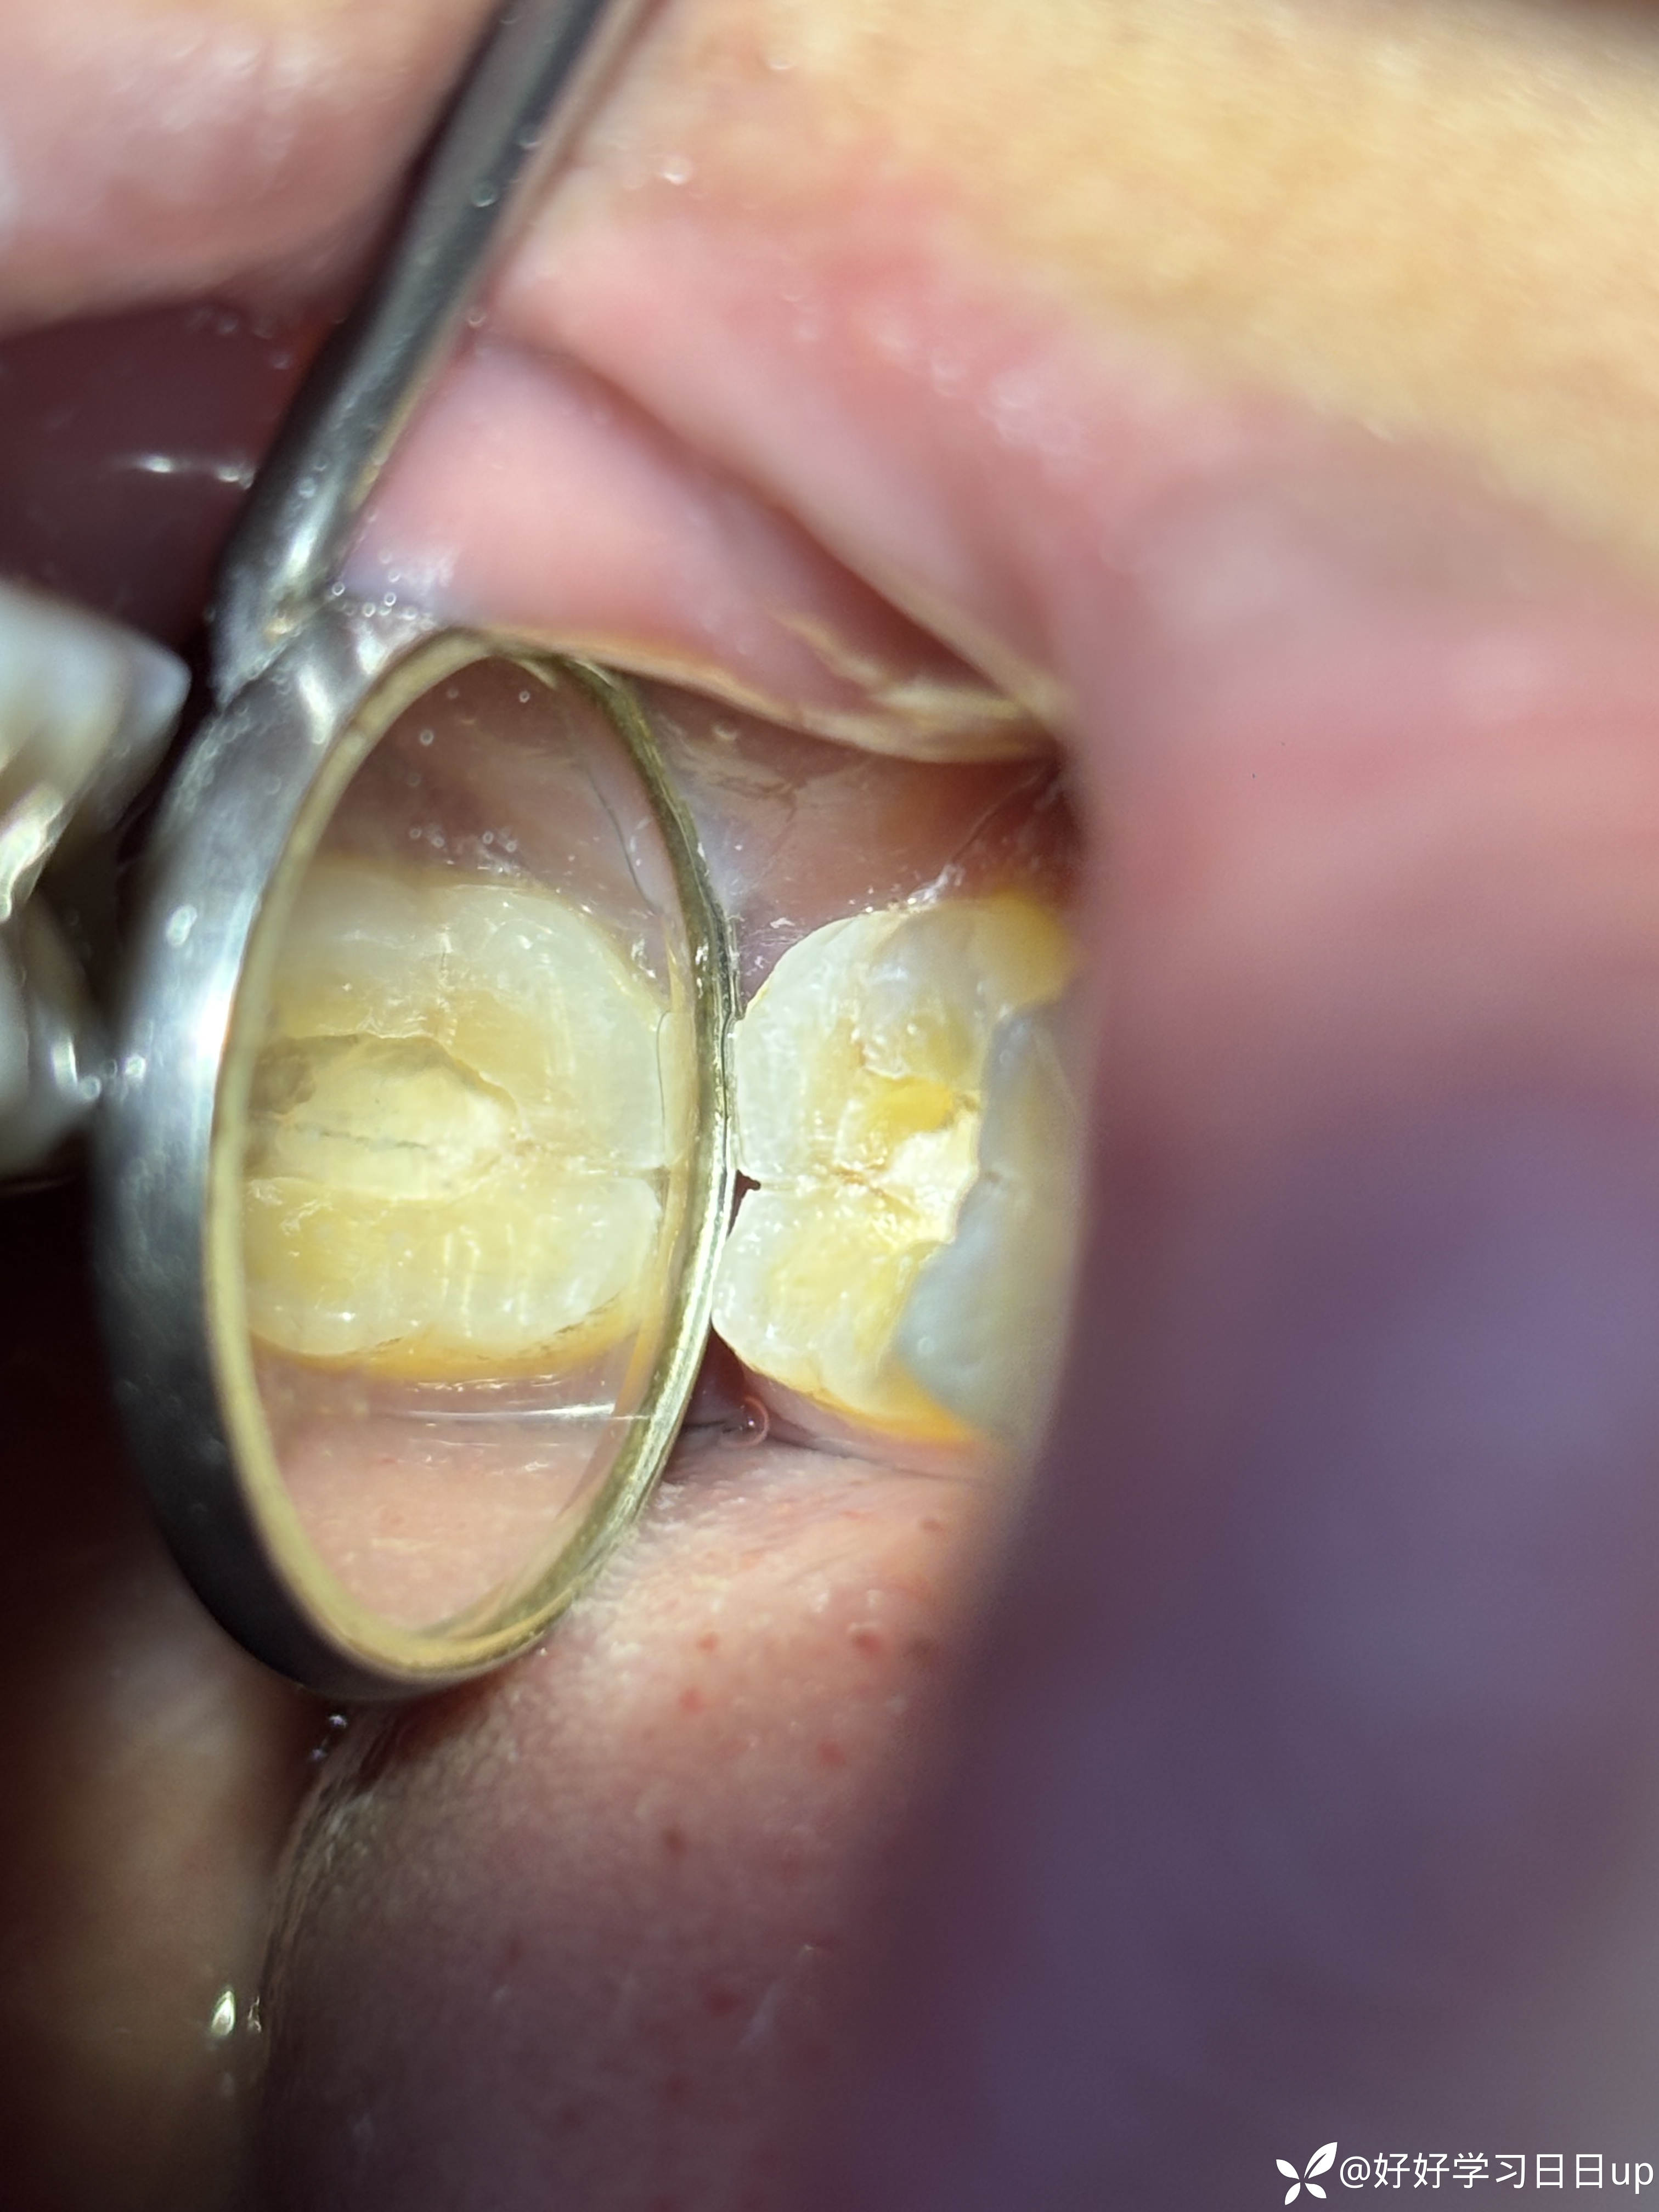

今天来了说肿了补的位置牙线用的过程中掉了一块,口内看可能是牙周脓肿,于是拍了一张根尖片,感觉不是根管引起的瘘管,引流脓液,洁治后,发现近中缺损部位疑似隐裂,拆除充填体发现隐裂贯穿近远中但是裂的位置卡不进探针,再次向下打磨隐裂部位,本来想完全去除隐裂,但没想到裂的还是比较深害怕抗力越来越差,跟患者说可能需要拔除,或者降低咬合后续观察,患者选择降低

我当时的想法是做一个树脂嵌体,但是想想好像也没作用,直接流体填起来降低到咬不到,颌面流体颊舌向做了一道杠想着给牙一个像中心的力量(瞎搞的也是没招了),老师们遇见这种是直接建议拔除还是有其他方法?是隐裂引起的脓包吗?